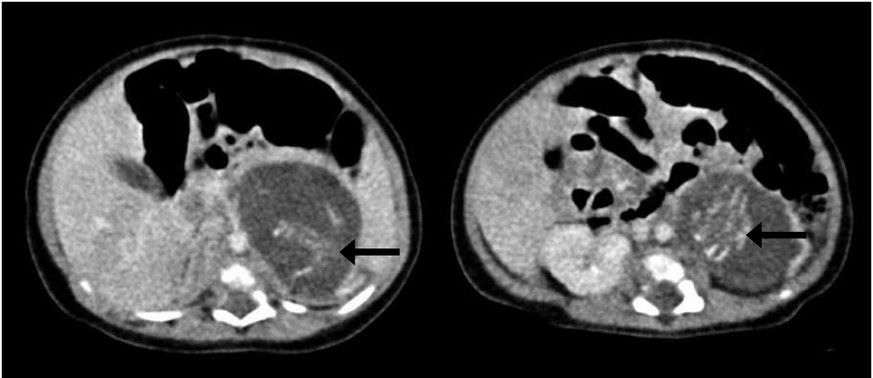

In einer Klinik in Hongkong wird ein Mädchen mit einem dicken Bauch geboren. Die Ärzte vermuteten bereits vor der Geburt einen Tumor. Doch als sie das Baby röntgen, stellen sie fest, dass sich in seinem Bauch zwei Föten befinden. Die Überreste seiner Geschwister.

Dieses äusserst seltene medizinische Phänomen nennt sich «foetus in foeto»: Im Mutterleib entwickeln sich zunächst mindestens zwei Föten und danach werden – anders als bei miteinander verwachsenen Siamesischen Zwillingen – ein oder mehrere Föten dem anderen einverleibt.

Die beiden Föten im chinesischen Mädchen waren im gleichen Stadium der Entwicklung, es handelte sich also sehr wahrscheinlich um Zwillinge. Sie wiesen Wirbelsäule, vier Gliedmassen, intakte Haut, Brustkorb, Darm, After, Genitalien und primitives Hirngewebe auf. Und sie waren mit einer Nabelschnur verbunden. (Wer sich das – etwas grausige – Bild des chinesischen Falls anschauen will – hier entlang!)

In ihrer Studie gehen die Ärzte davon aus, dass es sich um «kleine parasitische Föten» gehandelt haben muss, die sehr langsam gewachsen seien. Denn üblicherweise bemerken Ärzte sehr früh, wenn mehrere Föten in einer Gebärmutter sind, aber sich nur einer entwickelt, und die anderen verdrängt.

Dieses Mal nicht. Das Mädchen wurde im Alter von drei Wochen einer Operation unterzogen, wobei ihr die beiden Geschwister-Föten entfernt wurden. Alles lief gut, und die Kleine ist wohlauf.